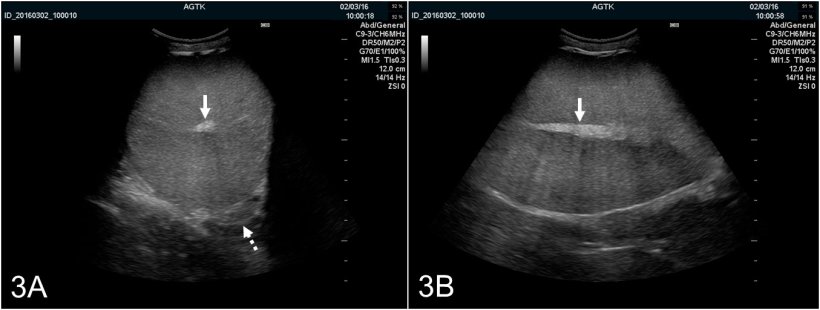

Os testículos podem-se scannear longitudinalmente ou transversalmente (figura 2A e B). Para determinar a circunferência do testículo, devem-se usar imagens transversais. O tecido testicular são tem uma ecogenicidade média e apresenta uma ecotextura homogénea, com o rete testis hiperecogénico no centro do testículo (figura 3A e B).